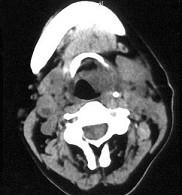

问题 女、54岁,鼻咽部异物感约三个月,PE:左侧声带固定,可见肿物,CT如图所示,应诊断为()

选项 A.喉部乳头状瘤 B.喉癌 C.喉部血管瘤 D.慢性增生性喉炎 E.增生型喉结核

答案 B